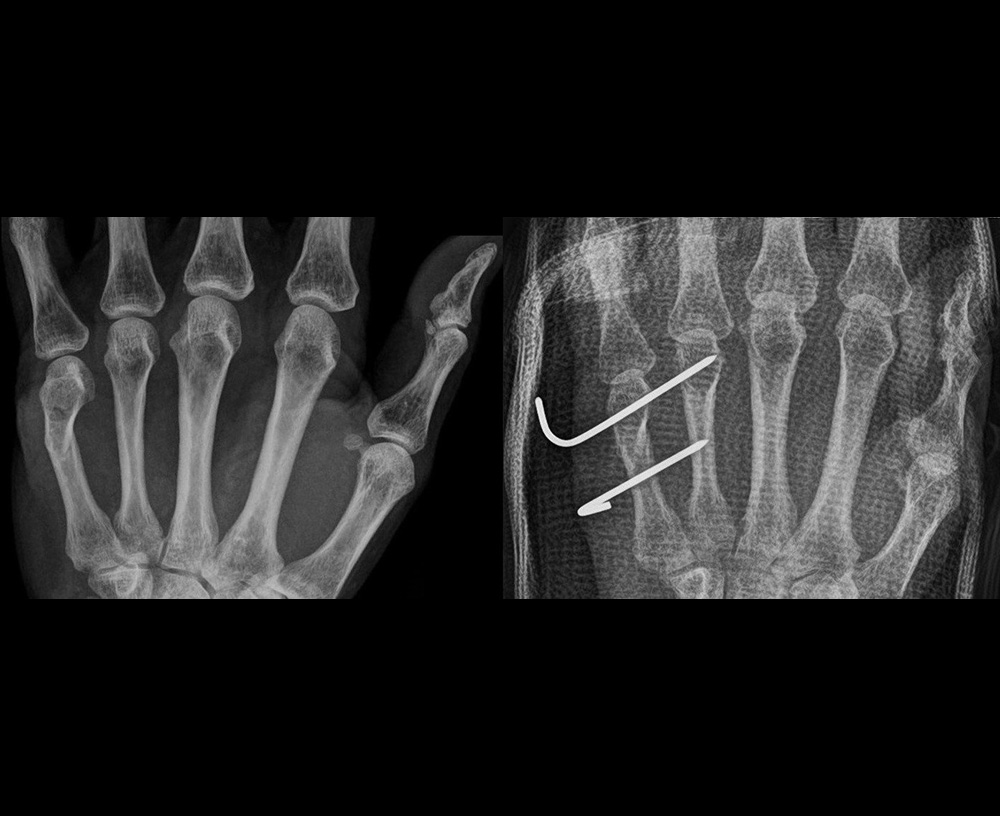

高齢者の方々によく起こる大腿骨頚部骨折(図1・図2)、肩から上腕の骨折(図3)、手関節周囲の骨折(図4)、人工膝関節置換術(図5)などの手術を行っております。

骨折経皮的銅線刺入固定

図4:骨折経皮的銅線刺入固定